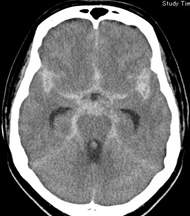

突然の激しい頭痛で発症します。脳動脈瘤の破裂によるものが多く、再破裂を防ぐため、開頭によるクリッピング手術やカテーテルによるコイル栓塞術など緊急治療が必要です。

下図のCT画像のように、クモ膜下出血では頭蓋底のクモ膜下腔に白い出血が広がり、頭部CTで確実に診断できます。クモ膜下出血と診断されれば、直ちに脳MRAや脳血管撮影で脳動脈瘤の部位を特定し、開頭クリッピング手術やカテーテルによるコイル塞栓術(血管内手術)が必要です。

クモ膜下出血は、通常耐え難い頭痛で急激に発症しますので、「頭痛が朝からだんだん強くなってきた」「頭痛があったが仕事を済ませてから受診した」というような訴えの患者さんは、クモ膜下出血でないことが多いのですが、ご心配な時は念のためCT検査をおすすめします。